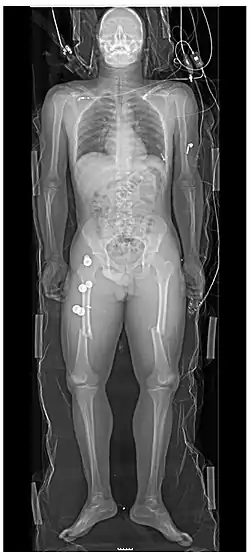

Whole-body radiograph of a major trauma case (where, however, full-body CT scan is usually preferable), showing bilateral femur fractures.[16]

A projectional radiograph of an extremity confers an effective dose of approximately 0.001 mSv, comparable to a background radiation equivalent time of 3 hours.[16]